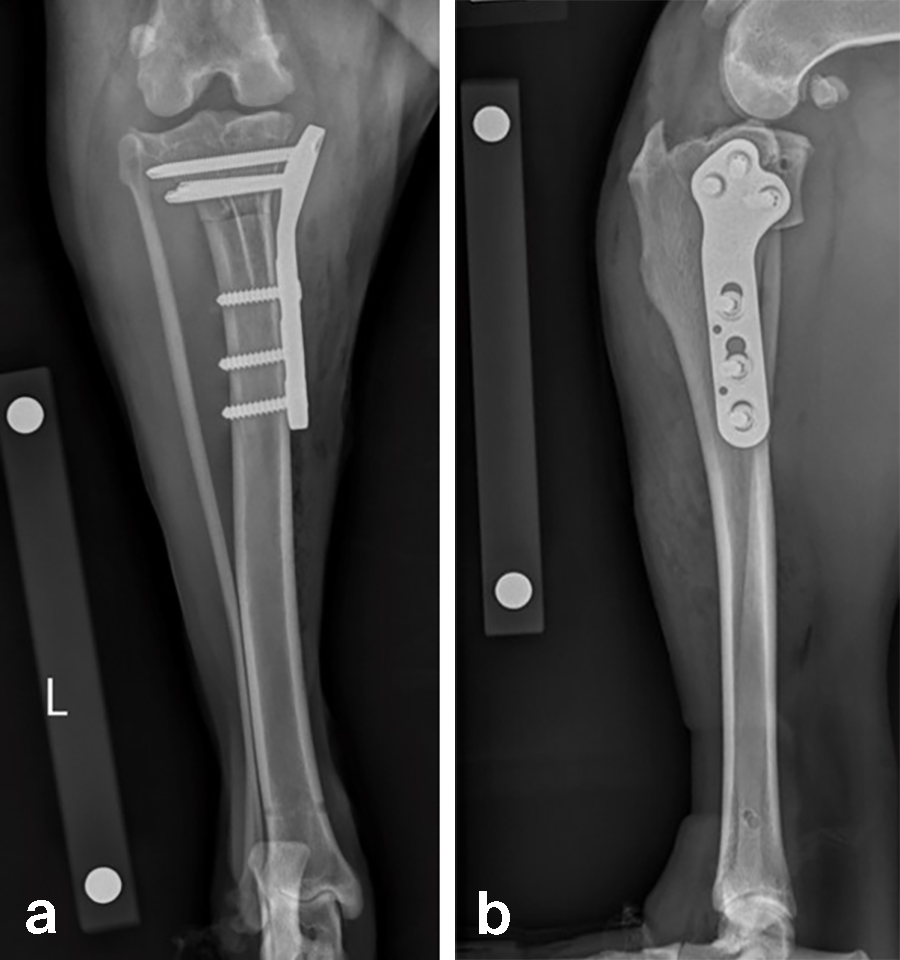

A 32 kg male neutered Golden Retriever presented with a recent deterioration of chronic right hind limb lameness. Physical examination revealed a cranial cruciate ligament rupture.

Follow-up x-rays at 8 weeks postoperatively revealed stable implants, stable bone segments, and healing of the osteotomy. The clinical outcome was satisfactory.